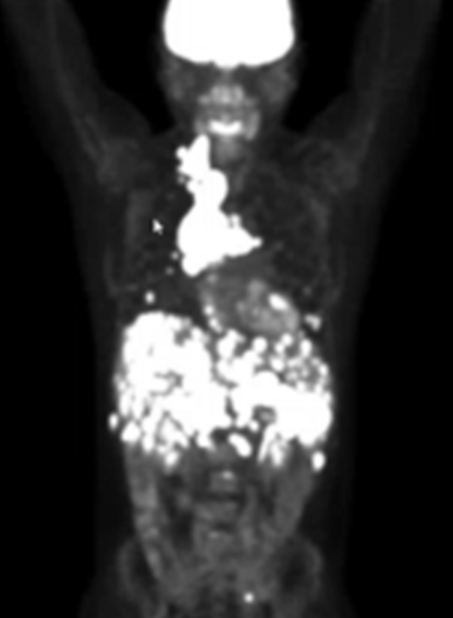

medical scan showing cancer in patient Erik Torres

This scan during Erik Torres' early treatment shows how pervasive his cancer was. Other than the brain tissue, all of the white signifies cancer.

A subsequent biopsy came back positive for cancer. After a week’s stay in the hospital, Erik was referred to a Dallas oncologist. A PET scan showed that the mass was much more insidious than anyone realized. Tumors crowded the space between his breastbone and spine, extending down to fill his entire abdomen. Cancerous cells surrounded his heart, and his liver had been infiltrated with tumors.